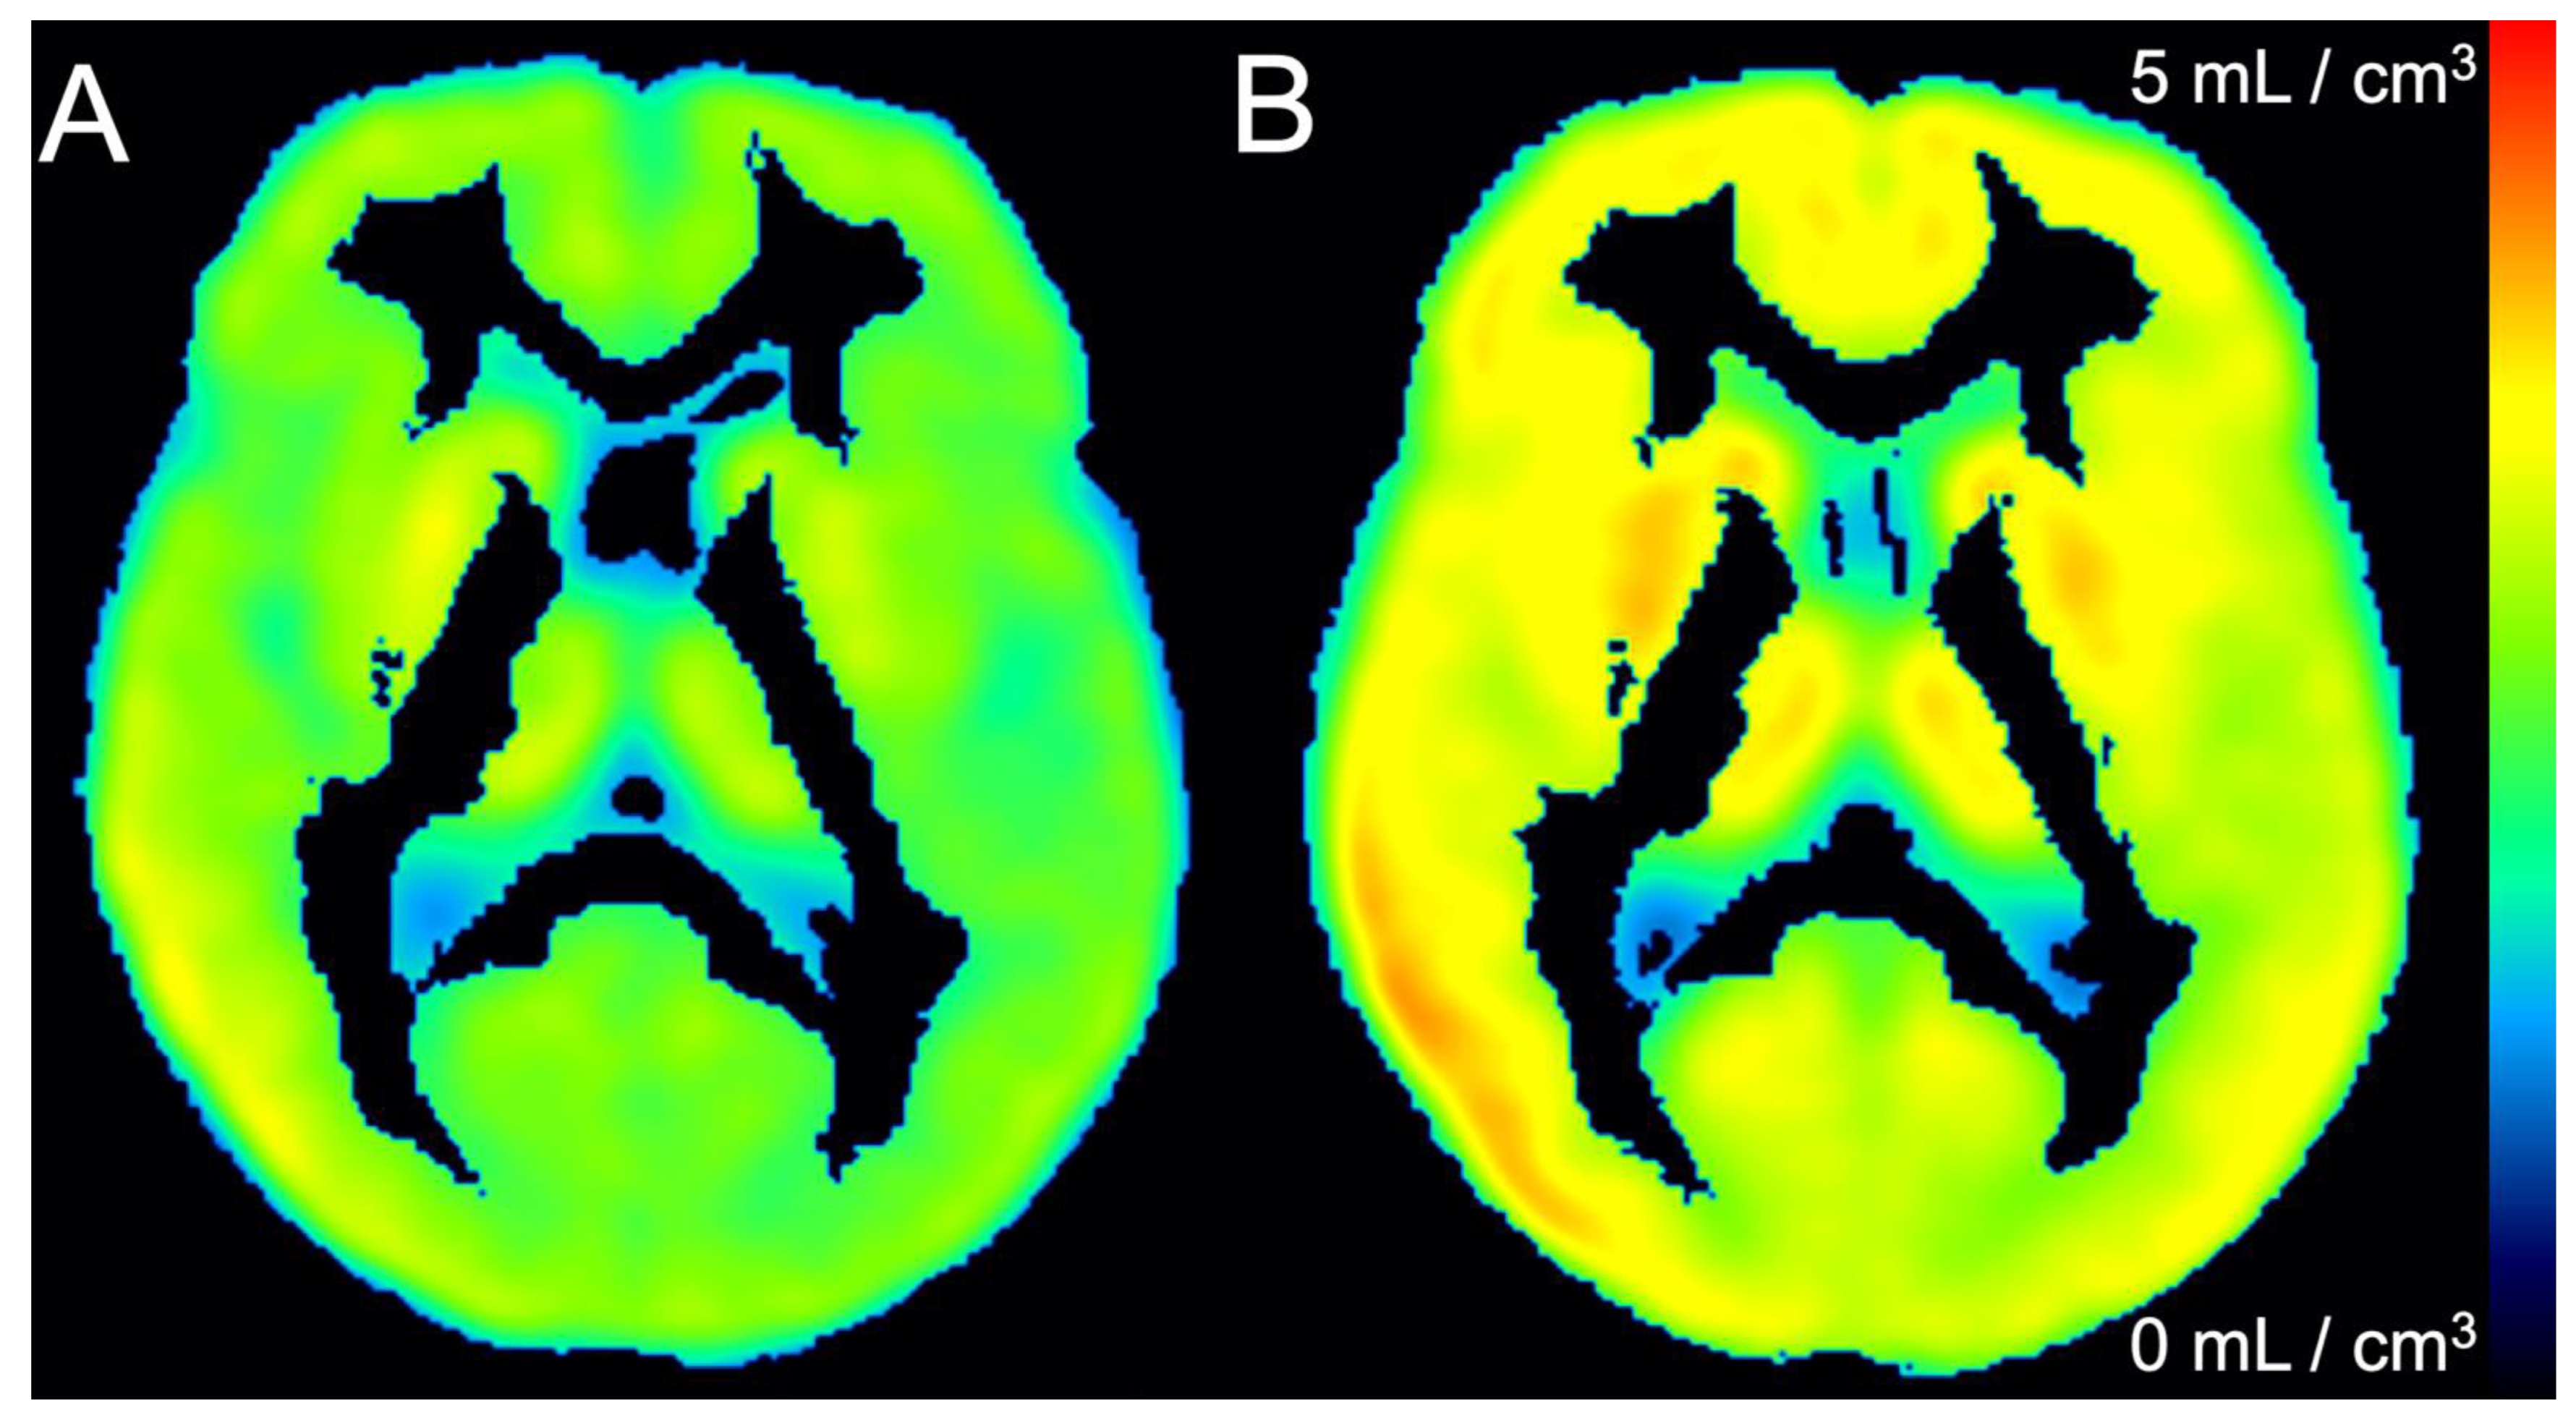

Kinetic Analysis: Whole brain [18F]NOS activity was well fit by models of reversible uptake, including 1TC r2 = 0.97 ± 0.02 and the Logan Plot r2 = 0.9999 ± 0.0001). VT calculated by 1TC and Logan Plot models were highly correlated (r2 = 0.97). Both graphical and 1TC models found significant whole-brain differences between HC and PD cohorts, including t-test comparisons of whole-brain Logan VT (p = 0.004) and 1TC VT (p = 0.008), as shown in Figure 4. VT differences between HC and PD cohorts were also observed in all 19 brain regions (p < 0.01). No significant whole brain difference was observed in K1 rate constants of [18F]NOS transport from blood to tissue (p = 0.72). VT parameter maps for each cohort showing regional variability are depicted in Figure 5. Spearman’s rank correlation coefficient did not reveal a significant relationship between UPDRS scores, including subscores and total score, and 1TC whole brain [18F]NOS VT (Supplementary Material).

Figure 5.

Mean one tissue compartment VT parameter maps of (A) healthy controls and (B) Parkinson’s disease patients.